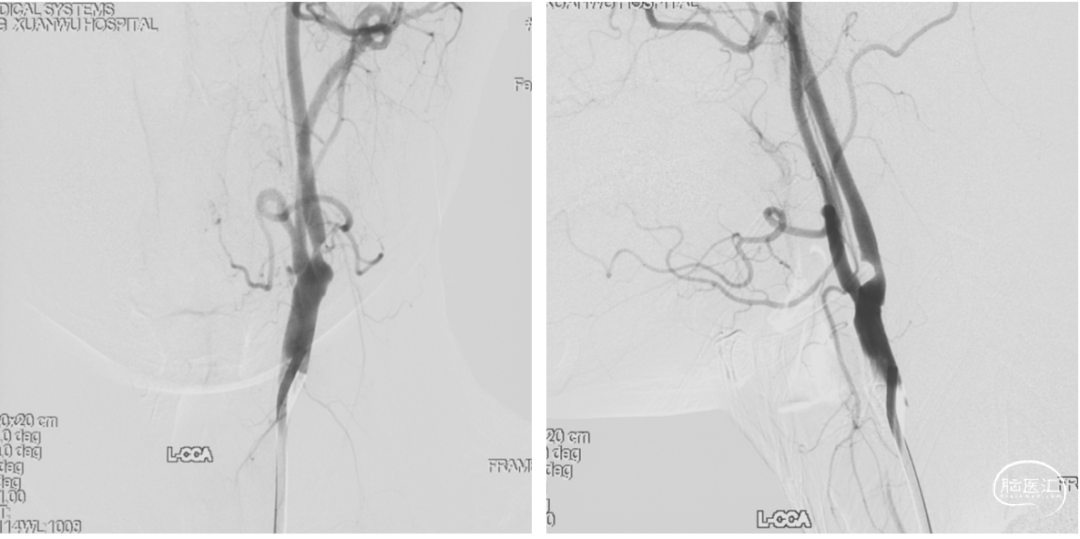

颈内动脉狭窄状况及闭塞试验

患者既往已行密网支架置入及颈动脉缩窄术,无介入治疗途径。

动脉瘤体积较大,且有增大趋势,需行孤立术保证动脉瘤内无血流。

2.本例患者动脉瘤体巨大,颈内动脉受累瘤化明显,密网支架放置中极易内陷入瘤腔,远端锚定不稳,最终导致支架释放失败;而支架远端落入瘤腔后,血流导向效果使瘤体进一步增大,视力受损症状加重。